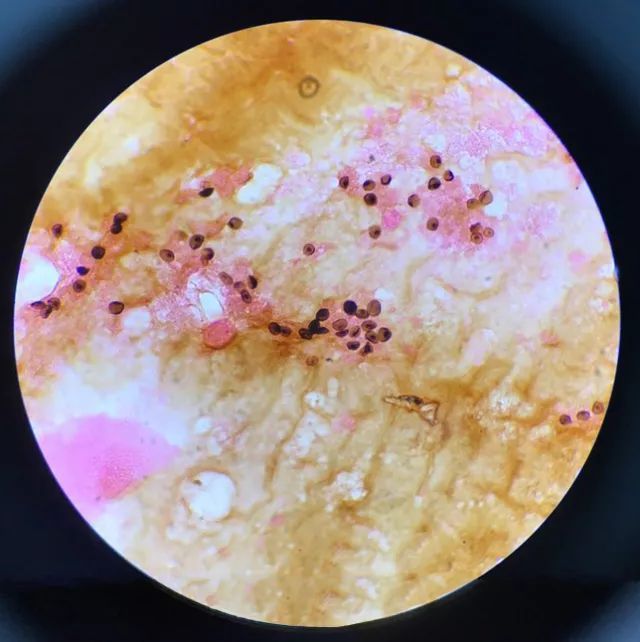

显微镜下的耶氏肺孢子虫

检验科室采用操作复杂、技术要求较高、难度较大的六甲基四胺银染色 (GMS) 法检测肺孢子虫包囊。经过一系列繁琐紧张的工作,经验丰富的检验技术人员在显微镜下成功找到耶氏肺孢子虫包囊,并查到了包囊典型的特征性括弧样结构,为临床提供了重要的诊断依据。